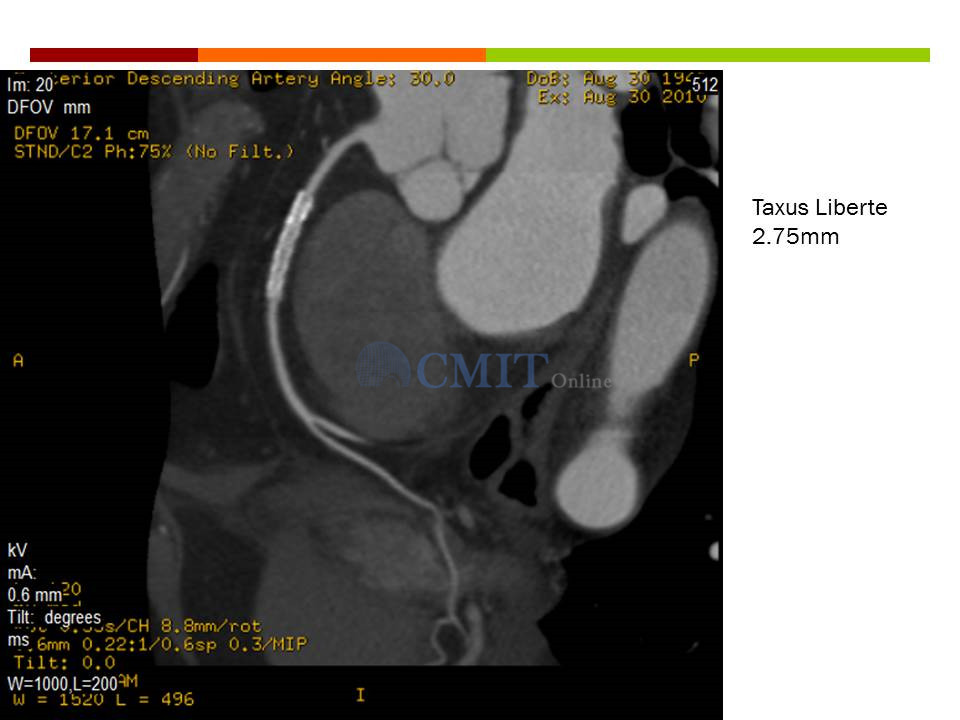

冠脉CTA读片技巧:如何判断支架内再狭窄?